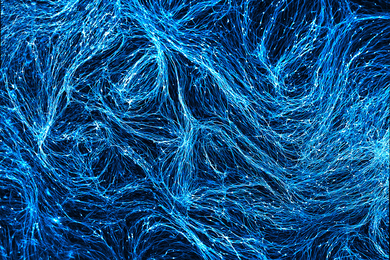

How 3D-printed models of neuronal axons could accelerate development of new therapies to treat neurodegenerative disorders.